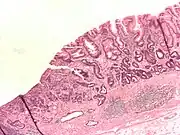

A stomach ulcer that was diagnosed as cancer on biopsy and surgically removed

Abnormal tissue seen in a gastroscope examination is biopsied by the surgeon or gastroenterologist. This tissue is then sent to a pathologist for histological examination under a microscope to check for the presence of cancerous cells. A biopsy, with subsequent histological analysis, is the only sure way to confirm the presence of cancer cells.[35]

• Gastric adenocarcinoma is a malignant epithelial tumour, originating from glandular epithelium of the gastric mucosa. Stomach cancers are about 90% adenocarcinomas.[67] Histologically, there are two major types of gastric adenocarcinoma (Lauren classification): intestinal type or diffuse type. Adenocarcinomas tend to aggressively invade the gastric wall, infiltrating the muscularis mucosae, the submucosa and then the muscularis propria. Intestinal type adenocarcinoma tumour cells describe irregular tubular structures, harbouring pluristratification, multiple lumens, reduced stroma ("back to back" aspect). Often, it associates intestinal metaplasia in neighbouring mucosa. Depending on glandular architecture, cellular pleomorphism and mucosecretion, adenocarcinoma may present 3 degrees of differentiation: well, moderate and poorly differentiated. Diffuse type adenocarcinoma (mucinous, colloid, linitis plastica or leather-bottle stomach) tumour cells are discohesive and secrete mucus, which is delivered in the interstitium, producing large pools of mucus/colloid (optically "empty" spaces). It is poorly differentiated. In signet-ring cell carcinomas, the mucus remains inside the tumour cell and pushes the nucleus to the periphery, giving rise to signet-ring cells.